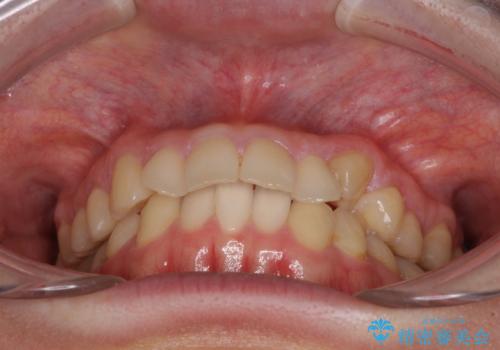

思っていた以上に上顎歯列を後方に移動させることができ、すっきりとした口元に仕上げることができました。

- 八重歯を気にして来院された患者様です。

診査を行ったところ、下顎前歯が1本欠損しており、下顎歯列が上顎よりも小さくなっていることで、上顎にデコボコが生じていました。

口元を見ると抜歯をして突出感を改善するような状態ではなかったため、上顎歯列のデコボコを整えて、歯列全体を後方に移動させることでバランスを取ることとしました。